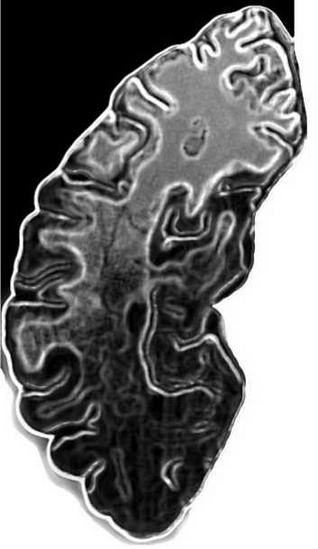

Нейрохирургические вмешательства остаются одной из самых сложных операций в медицине. Тем удивительнее, что еще 7000 лет назад люди отваживались на подобные операции, высверливая отверстия в костях черепа. Можно предположить, что в каменном веке, среди воинов, а также охотников, нападавших на крупных животных, черепно-мозговые травмы, в том числе переломы костей черепа, были не таким редким событием. Возможно, поэтому трепанация черепа — вскрытие его свода — стала одной из древнейших операций, которую лекарям той эпохи приходилось проделывать над своими соплеменниками.

Операция эта производилась значительно чаще, чем мы можем себе представить. Все начиналось, быть может, с удаления инородных предметов, например, наконечников оружия, вонзившихся в кость черепа. Что ждало прооперированного? Нередко — жизнь, как свидетельствуют находки, относящиеся к эпохе неолита.

Так, на черепе возрастом 6500 лет, найденном в Германии, в местечке Йехтинген, заметна новая, наросшая костная ткань вдоль края зоны трепанации. Это свидетельствует о том, что пациент перенес хирургическое вмешательство, и рана, нанесенная врачом, стала заживать.

Следы заживления видны и на черепе человека, жившего 7000 лет назад в Энисхайме, в Эльзасе. Возможно, это — древнейшая в мире находка со следами трепанации. Этот человек жил в эпоху, когда население Центральной Европы только переходило к оседлому образу жизни. На черепе «эльзасского пациента» зияют сразу два поразительно больших отверстия диаметром 6 и 9 сантиметров. По оценке экспертов, даже после таких операций он прожил еще несколько лет.

В распоряжении ученых имеются сейчас сотни черепов, датируемых каменным веком, и в 70-80% случаев больные оставались в живых даже после такого радикального лечения. Эффективность тогдашних эскулапов просто поражает.

По имеющимся находкам ученые восстановили последовательность оперативного вмешательства. Хирурги каменного века осторожно соскребали кость, удаляя слой за слоем. Это проделывалось свежесколотыми пластинами кремня. Их преимущество было не только в острых, как бритва, краях, но и в относительной стерильности. Современные врачи похвально отзываются и о выбранном методе — соскребании кости. Это было куда лучше, чем пробивать голову пациента, что могло бы непоправимо повредить мозговую оболочку, лежащую непосредственно под черепной костью.

Череп с признаками трепанации из погребения в Кричел Даун (Англия)

Эта оболочка защищает головной мозг от проникновения инфекции. Если в крохотном зазоре между сводом черепа и мозговой оболочкой растечется кровь или образуется доброкачественная опухоль, то головной мозг будет испытывать сильное давление. В этом случае, чтобы помочь больному, нужно проделать отверстие в черепе, не допуская при этом повреждения мозга.

В археологии давно возобладало мнение отом, что трепанация черепа производилась лишь в ритуальномагических целях. В эту концепцию вполне вписываются амулеты в виде так называемых трепанационных дисков — костяных дисков, имеющих ту же форму, что и отверстия, проделываемые в черепе. Кстати, до сих пор встречались, главным образом, черепа мужчин со следами трепанации, что заставило предположить, будто в этих гипотетических ритуалах участвовали только мужчины.

Однако исследование найденных черепов методами компьютерной томографии убедило ученых в том, что причины, побуждавшие препарировать черепную кость, чаще всего были чисто медицинскими. Это было именно лечение больных людей. Особенно часто врачи вмешивались, устраняя последствия кровоизлияний, вызванных сильным ударом по голове, нанесенным, например, копытом животного или человеком. Чтобы дать разлившейся крови стечь, пациенту вскрывали череп. В противном случае он мог умереть. Трепанация производилась и для того, чтобы извлечь расщепившиеся кости черепа, если голова человека была проломлена, и чтобы удалить (или выпрямить) вмявшийся от удара кусок кости.

Все это заставляет ученых с сомнением относиться к гипотезе об использовании трепанации исключительно в ритуальных целях. Впрочем, женские черепа со следами такого лечения по- прежнему попадаются крайне редко. Одна из возможных причин — женщины редко охотились или воевали, а потому шанс получить серьезную травму головы был для них значительно ниже, чем для мужчин.